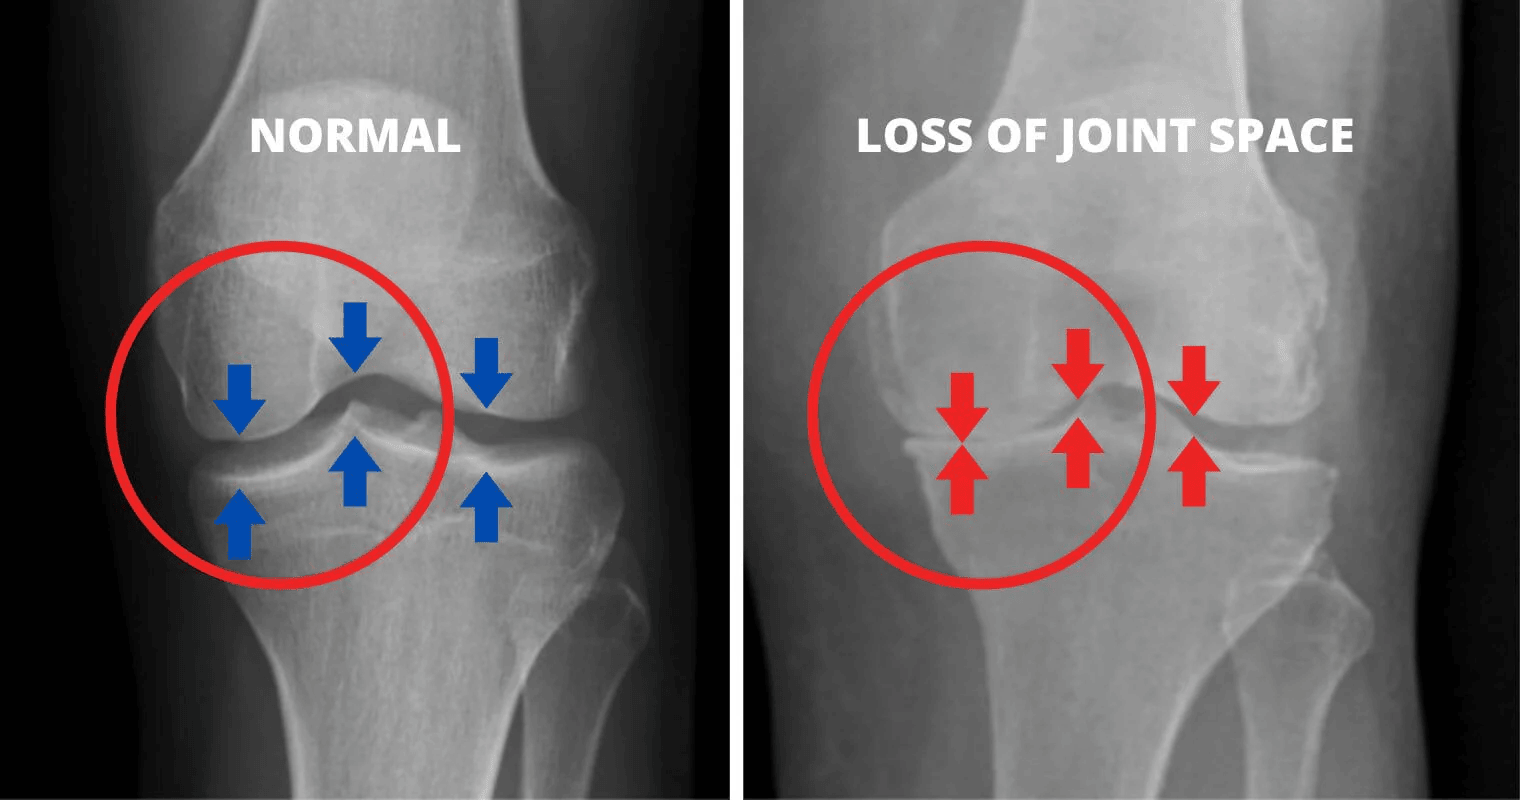

What if I told you that the pain and stiffness you feel are caused by the wear and tear of your cartilage, leading to uncomfortable friction?

As the cartilage wears away over time, the bones start to rub against each other, causing intense pain and discomfort. This friction leads to discomfort, swelling, and a significant reduction in mobility.

As you age and continue to put stress on your knees, the cartilage deteriorates. And when this happens, you start experiencing severe pain due to the bones rubbing together.